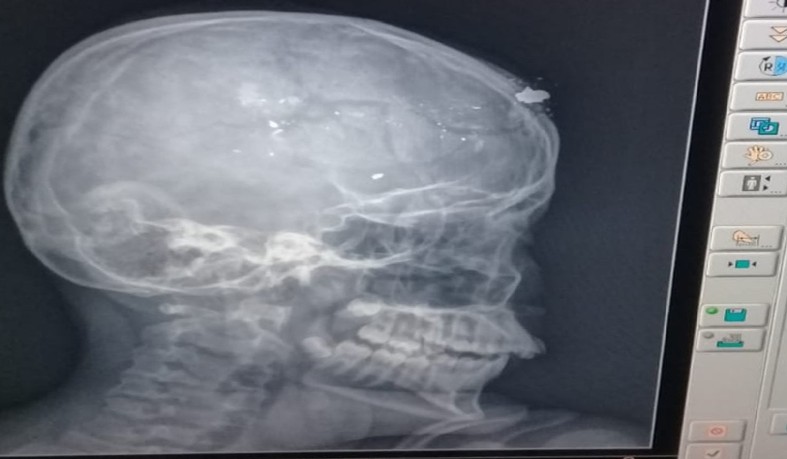

Ainda segundo a polícia, o adolescente, de 14 anos, e o irmão, de 12 anos, estavam brincando com o revólver do pai quando a arma disparou acidentalmente no mais novo. Segundo o G1, ele foi atingido na nuca, teve o crânio fraturado e fragmentos de bala saíram pela testa.

O adolescente foi socorrido para o Hospital Regional de Catolé do Rocha e depois foi encaminhado para o Hospital de Trauma Campina Grande. Segundo o hospital, a vítima encontra-se na UTI infantil em estado de saúde grave.